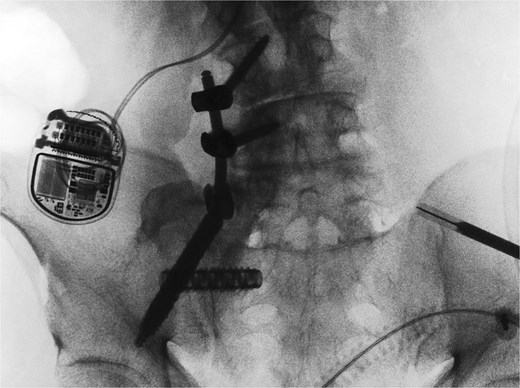

A CT of the pelvis showed significant hyperostosis along the anterior right SI joint and a pseudoarthrosis between the L5 transverse process and the sacral ala that was osteoblastic-appearing in nature (Fig. 1). A SPECT-CT demonstrated increased uptake along the same area, suggestive of inflammatory degenerative changes (Fig. 2).

Coronal (left) and axial (right) views of pelvic CT-SPECT highlighted increased uptake along the right SI joint, suggestive of inflammation (arrows).